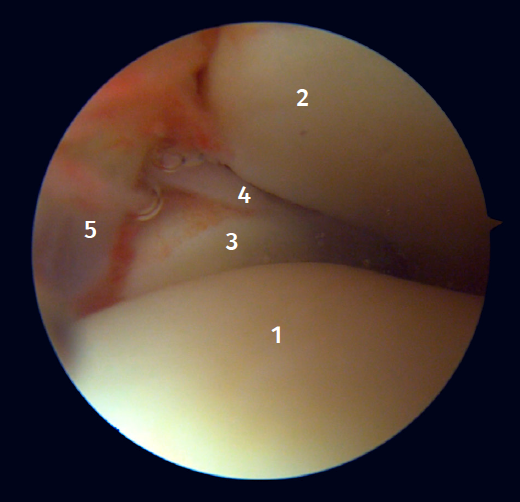

Arthroscopic anatomy of the syndesmosis

Anterior arthroscopic view

Twenty percent of the ATFL is intra-articular(7). On adopting an anteromedial access of the ankle, directing the arthroscope laterally, we can see the distal fibers of the ATFL with their oblique distribution and their continuation with the anterior talofibular ligament (Figure 2). If we move into the tibiotalar joint, we see the distal tibiofibular joint with the syndesmotic recess occupied by synovial tissue (Figure 3).

Posterior arthroscopic view

From the posterolateral approach we identify the lateral (fibular) malleolus and, from here, we visualize the intra-articular fibers of the PTFL, which run obliquely and insert into the distal portion of the tibia. We also see the distal thickening of the PTFL (transverse ligament) in continuity with the posterior lip of the distal tibia (Figure 4).